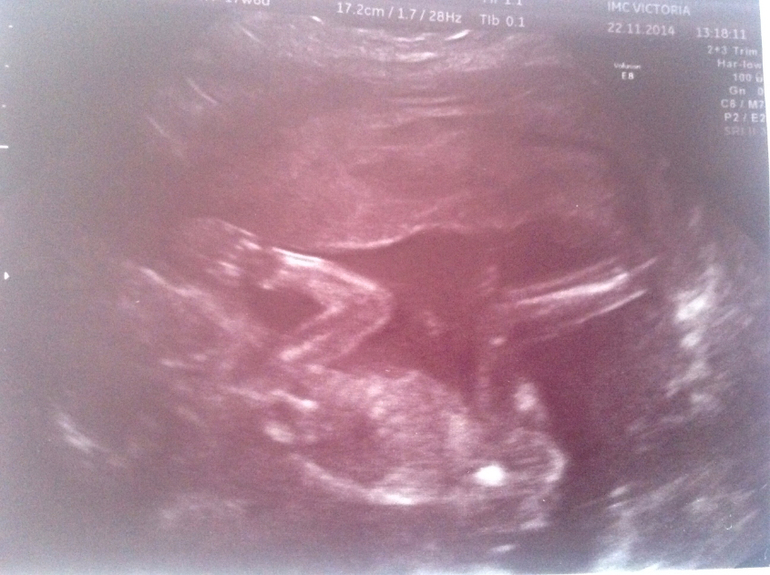

Вот и мы вчера прошли наш долгожданный скрининг, ходили с мужем в его день рождение платно к одному из лучшей врачей Иркутска, врач нам очень понравилась, всё подробно рассказала, показала!)) первые фразы: ребёночек лежит в низ головой, ой да это девочка у нас!)) так что ждем нашу долгожданную девчушку)))

Нам наконец-то рассчитали с учетом моего короткого цикла срок Б и ПДР. 18 неделек и 3 дня, и мы доросли на этот срок, на первом скрининге отставали на 5 дней. ПДР 22.04.2015. Весим мы уже 240гр, все косточки и органы в норме, всё хорошо функционирует))) наш папа был очень доволен)) малышка сначала спала, потом проснулась, но личико никак показывать не хотела, помахала нам ручкой и пинала ножками)) я бы вечно могла лежать и наблюдать за нашей крошкой, это так приятно)))